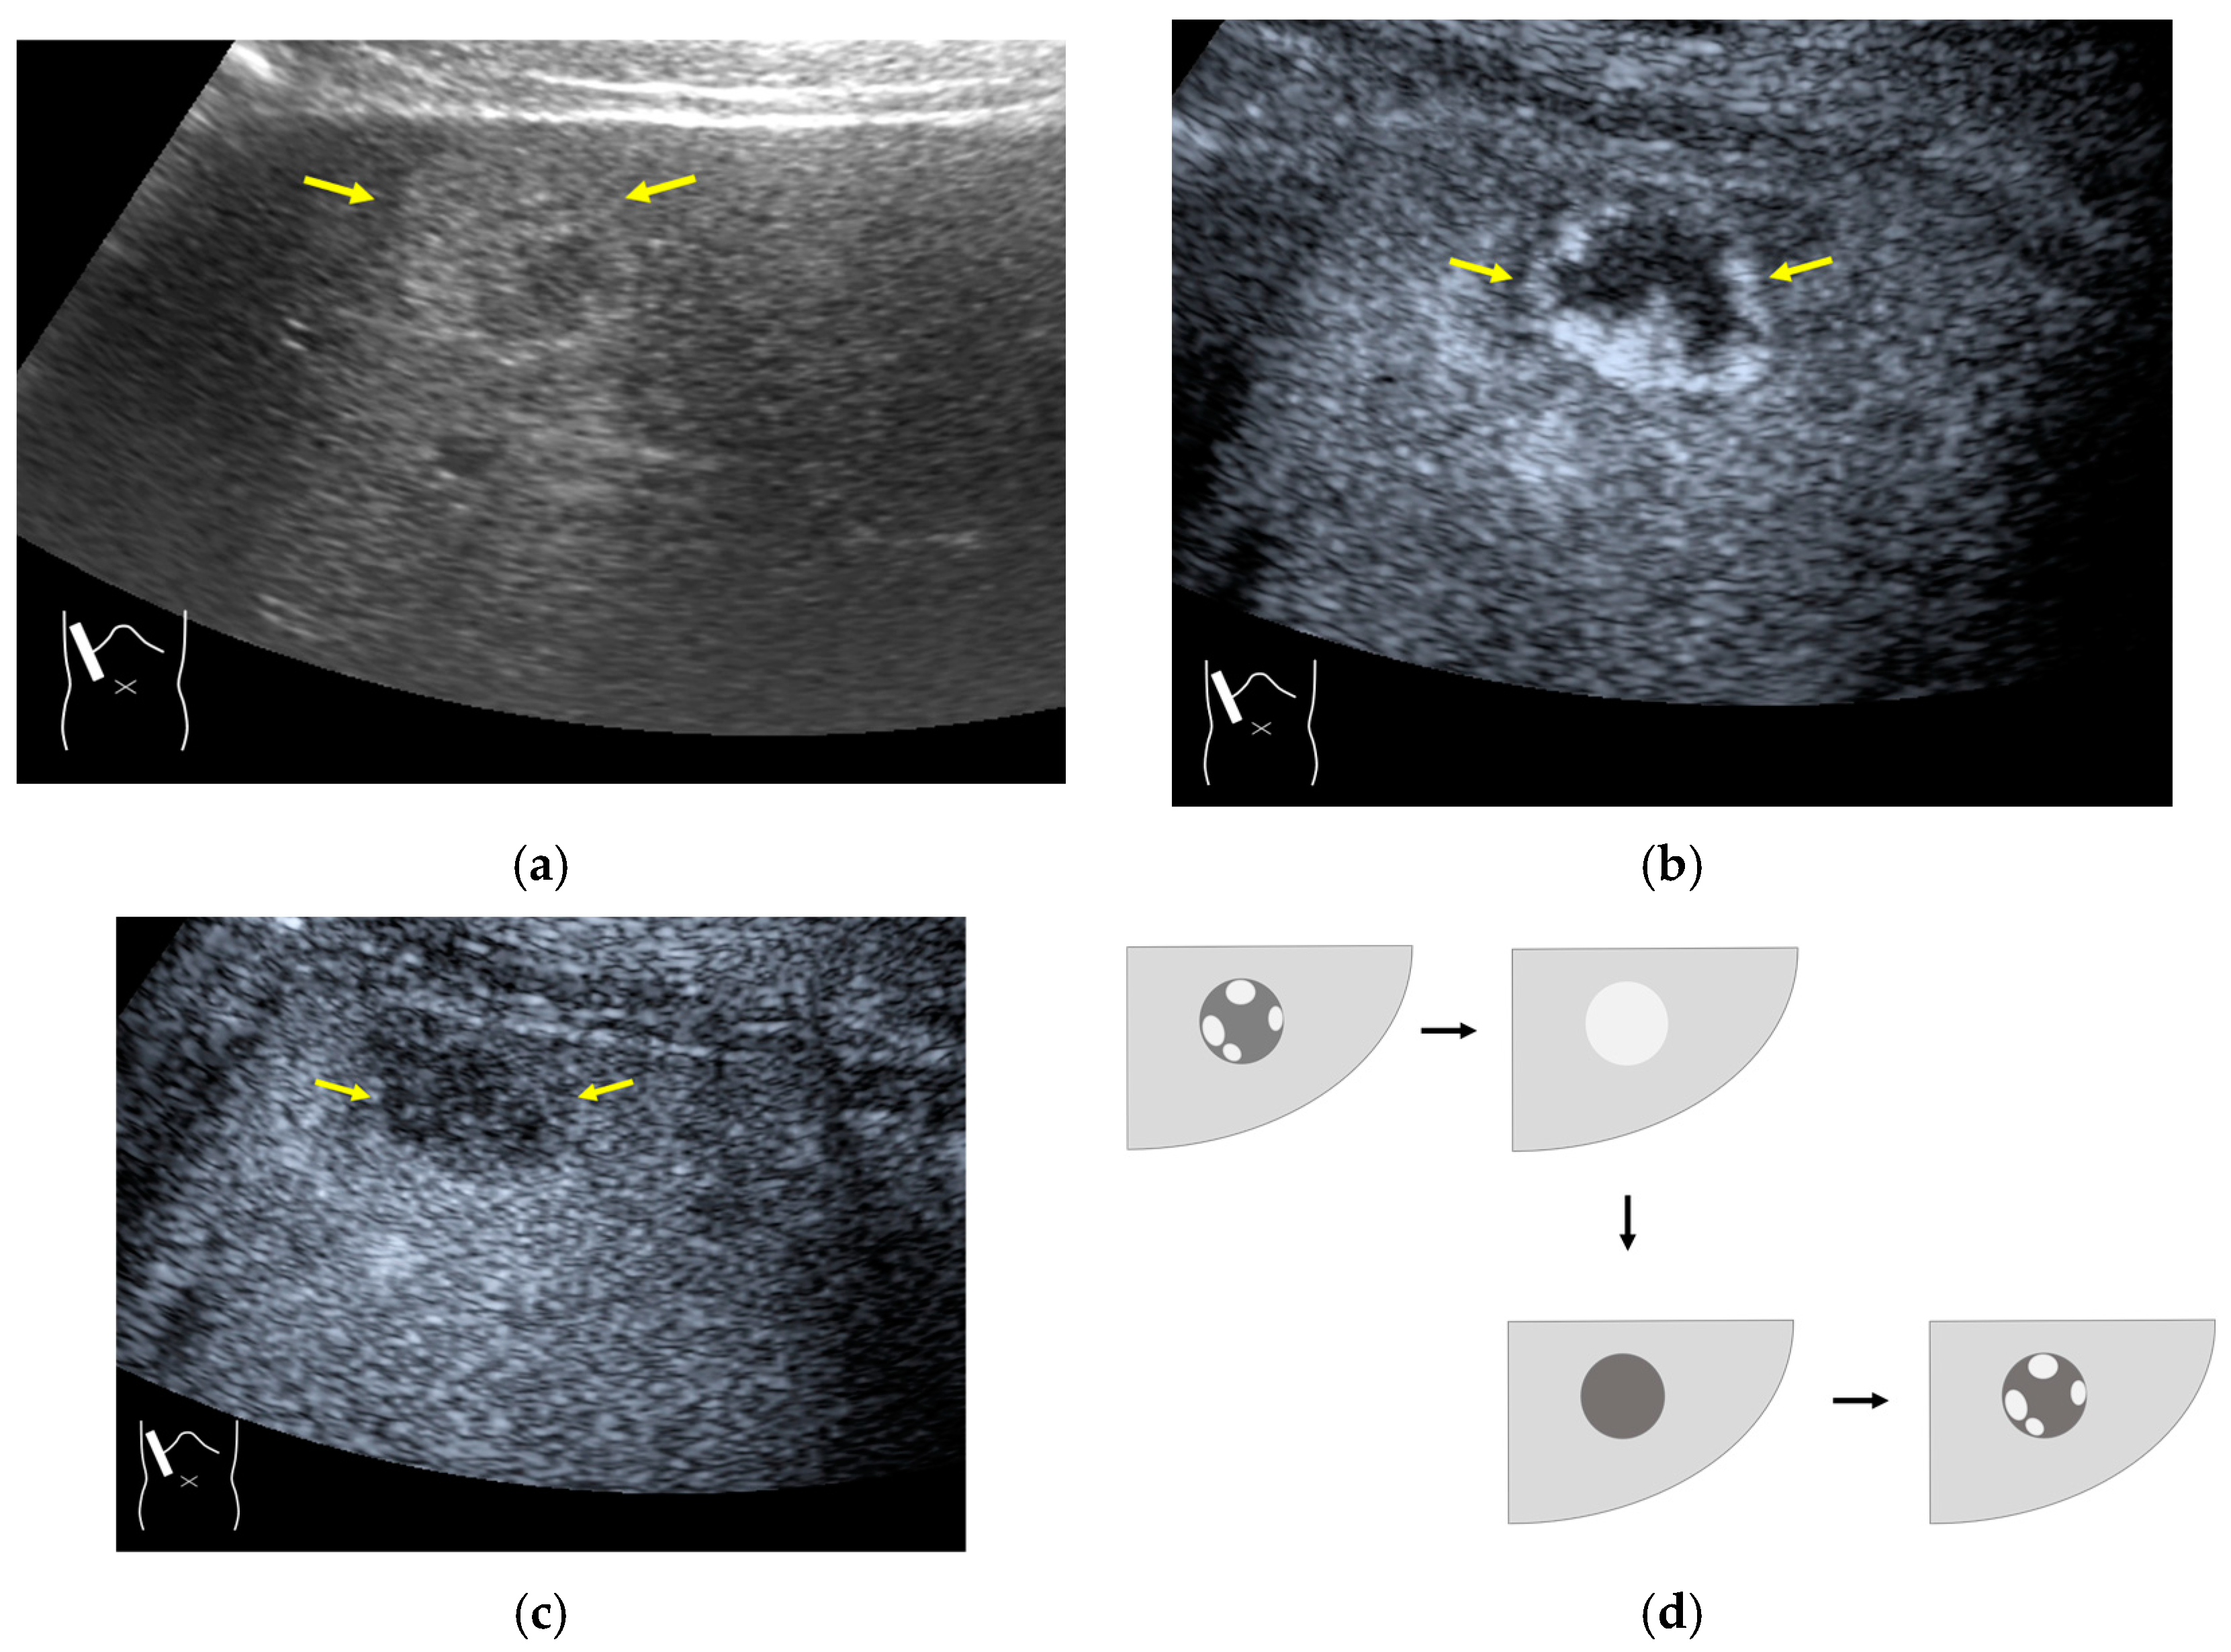

3.2.2. Prolonged Heterogeneous Accumulation Artifacts

Prolonged heterogeneous liver enhancement (PHLE) is a well-known CEUS artifact [28,55], and it is characterized by the appearance of “cloudy” or “wool-like” heterogeneous enhancements in the liver’s periphery [28,55]. PHLE begins to appear within 2–6 min after contrast injection (Figure 13). Despite having no clinical significance, this phenomenon has important negative impacts on CEUS diagnosis, as it mimics focal lesions [56], intrahepatic vascular anomalies [57], or portal vein gas [58]. Although there is no established mechanism for the appearance of this phenomenon, it is assumed that, as shown in Figure 12, the contrast agent that would normally flow through the portal vein as uniform granules and uniformly reach the hepatic periphery as non-uniform granules (due to contrast agent or other causes) in the hepatic periphery, and the areas with a high concentration of the large-diameter contrast agent are expressed as heterogeneously enhanced areas. However, the precise microcirculatory and basic mechanisms leading to this phenomenon remain only partially understood, and no satisfactory conclusions have been reached. However, the occasional inhomogeneity of the diameter of the contrast agent in the portal vein is clearly recognized in recent microflow imaging (Figure 13) [59]. Although detailed proof will require many experiments and clinical cases, we hope that microflow imaging will provide a new perspective that will help to clarify these artifacts. The most useful artifact avoidance strategy is to confirm the phenomenon’s instability by changing the examination conditions.

Figure 13.

Prolonged hyperenhancement. (a) CEUS image in the postvascular phase. Hyperenhanced areas (arrows). (b) Superb microvascular imaging reveals many aggregated bubbles passing in the portal vein (arrows).

3.2.3. CEUS-Related Posterior Echo Enhancement

CEUS-related posterior echo enhancement (PEE) differs from that of B-mode US. PEE is the most easily recognizable US artifact, and it is characterized by an echogenic band behind a lesion with sonographically different characteristics. In B-mode US, PEE is thought to be secondary to changes in the attenuation of US beams. The area distal to a less attenuating lesion exhibits an increased US intensity and is brighter than it would be without the lesion [60,61]. Posterior echoes are also considered to be strongly related to sound refraction, which occurs when the US beam strikes the interface between two media with different acoustic velocities at an oblique angle of incidence [62]. Whether the US beams converge or diverge depends on the form of the interface and whether the sound path is from a high-velocity medium to a lower-velocity medium or the opposite. The latter condition is thought to give rise to PEE. Aside from these well-known causal factors, there are many other factors contributing to PEE, including reverberation. In brief, PEE remains a multifaced entity featuring complex interplay among sound attenuation, sound refraction, sound reverberation, and other factors. In the clinical setting, hemangioma [63], hepatocellular carcinoma [61], and hepatic cysts are known to cause PEE. We sometimes encounter CEUS-related PEE in daily CEUS examinations. It is characterized by the sudden appearance of a highly echoic zone during CEUS at a location where there was no highly echoic zone in B-mode US (Figure 14). Although this phenomenon’s mechanism of appearance has not been fully elucidated, the most plausible explanation is that many scattered signals emitted from the contrast agent, which rapidly flow into the lesion, interfere with each other inside the stained area, and the reflected time-delayed signals return to the transducer with a certain delay, resulting in the appearance of a highly echoic zone behind the lesion. The precise mechanism of CEUS-related PEE is a problem to be resolved in the near future.

Figure 14.

Posterior echo enhancement appearing during CEUS. (a) Gray-scale US of the case (arrows). (b) CEUS image of the lesion (focal nodular hyperplasia) (arrows). (c) CEUS image of posterior enhancement (arrow heads). Posterior echo enhancement appears immediately after the mass is rapidly and homogeneously enhanced. (d) Reasonable explanation of this phenomenon. Many scattered signals emitted from the bubbles that rapidly enter the mass lesion interfere with each other inside the stained area, and these scattered signals return to the transducer with a certain time-delay. These time-delayed signals are displayed as a PEE. Black circle: mass lesion; small blue circles: CEUS bubbles; red solid line: ultrasound beam; red dashed line: ultrasound is expected to travel; red arrows: reflection between bubbles.